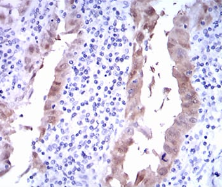

IHC    1/200 - 1/1000